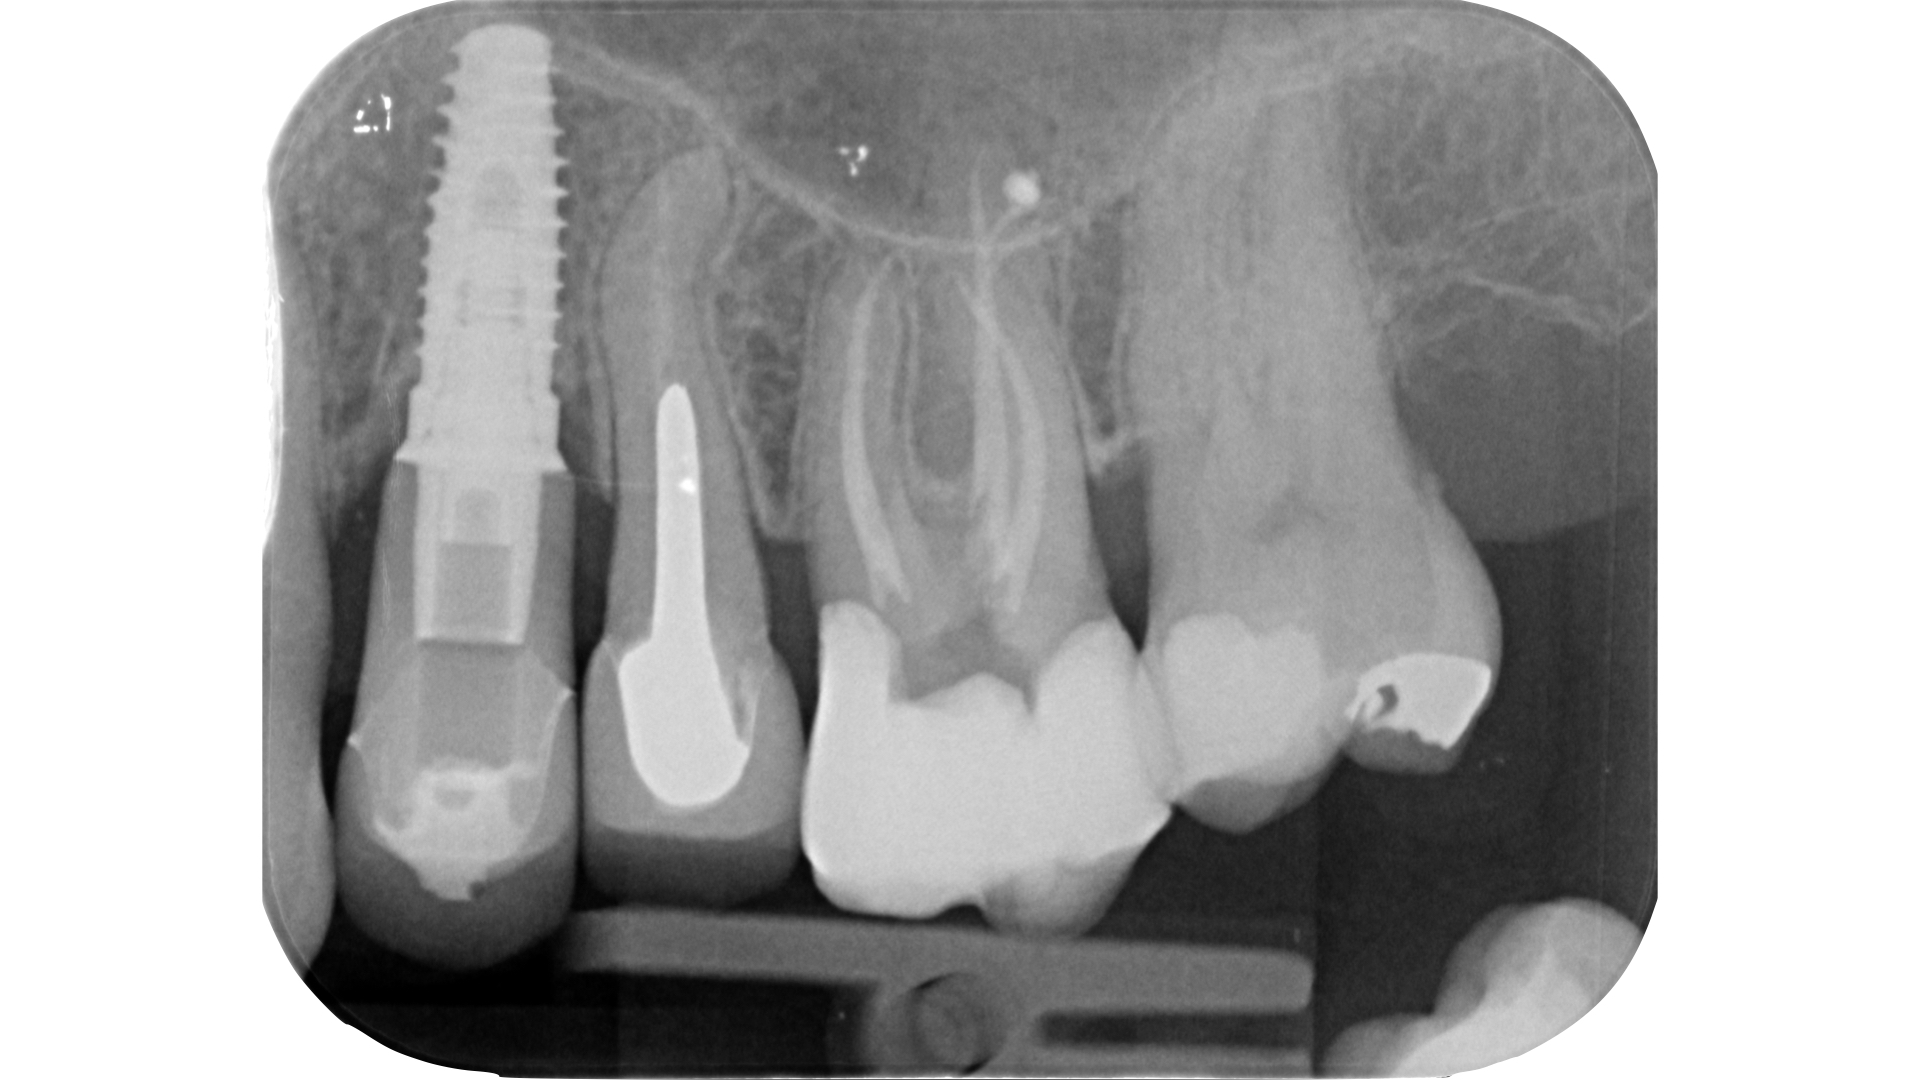

Lo step successivo, ossia l’esplorazione manuale e meccanica del sistema canalare, potrebbe nei casi più complessi essere impedito a causa dell’ostruzione dell’orifizio. Una calcificazione che si estende più in profondità rispetto al pavimento della camera pulpare può infatti rendere impossibile il sondaggio anche con lo strumento più piccolo a disposizione.

L’ostruzione, se estremamente limitata, può essere bypassata con un file montato su manico (micro-opener 10.04 15.04, Dentsply): questo strumento permette ottima visibilità e sensibilità rispetto ad un classico file manuale (Figure 21-26).